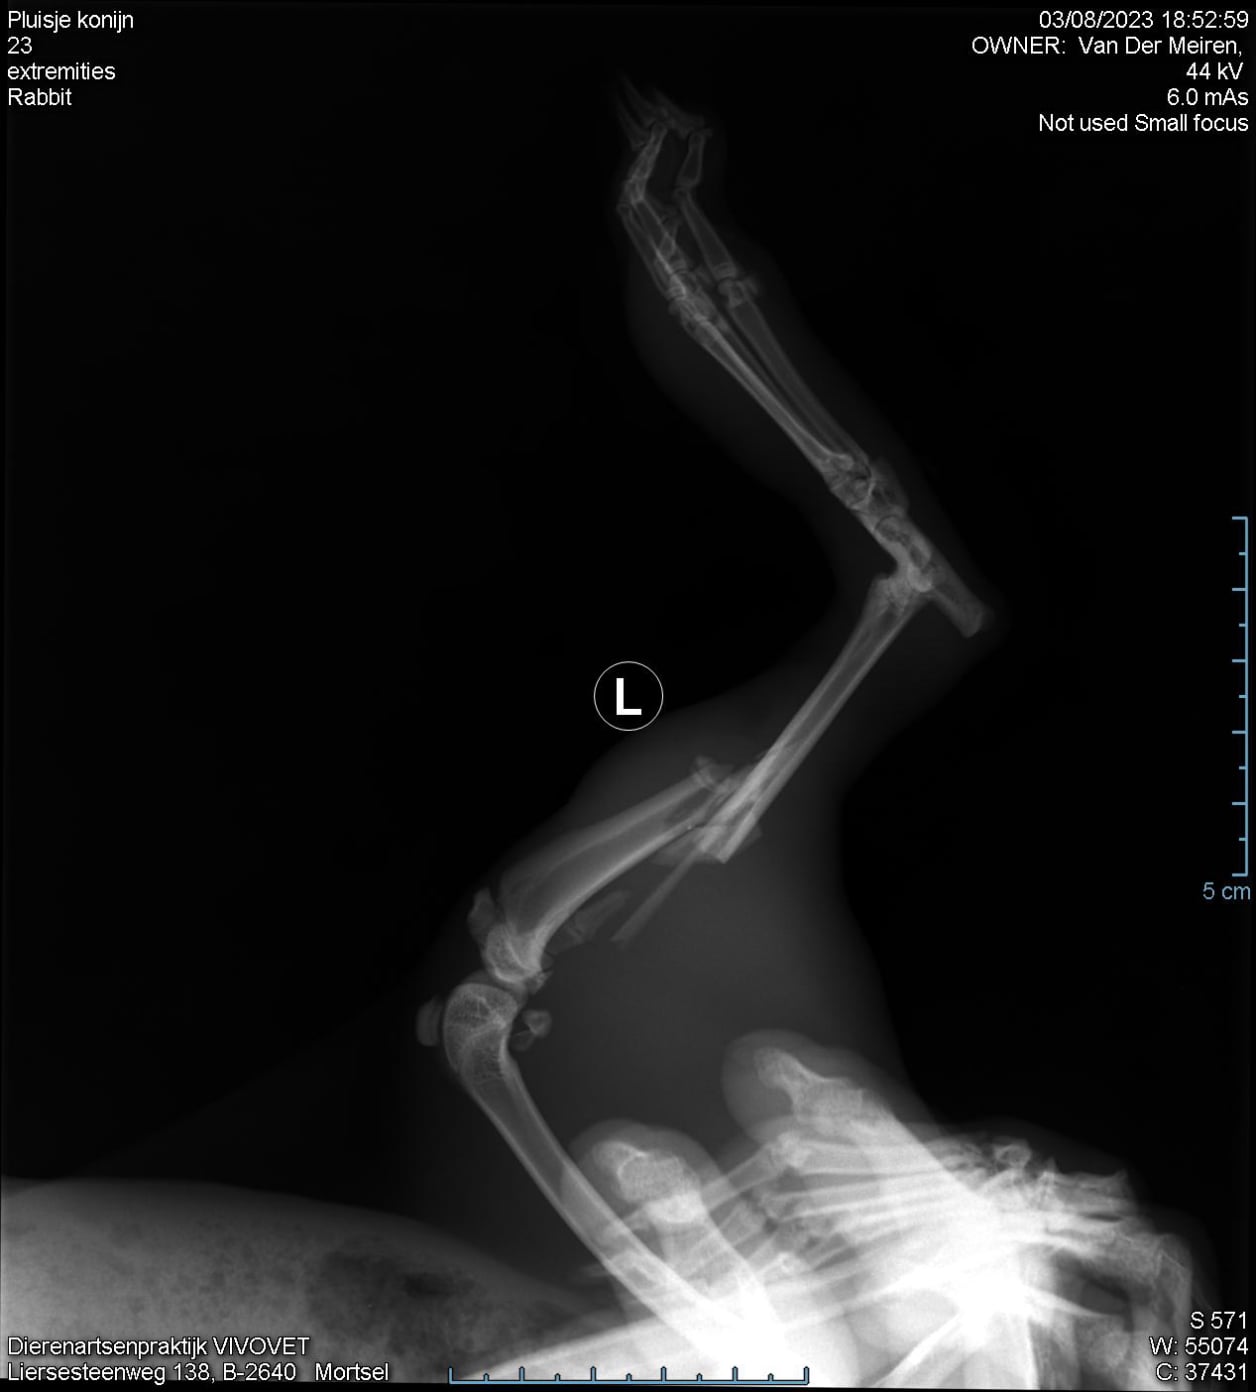

Op de RX opname is een verplaatste breuk te zien.

De poot slingerde heen en weer. Pootamputatie was in dit geval de enige oplossing.